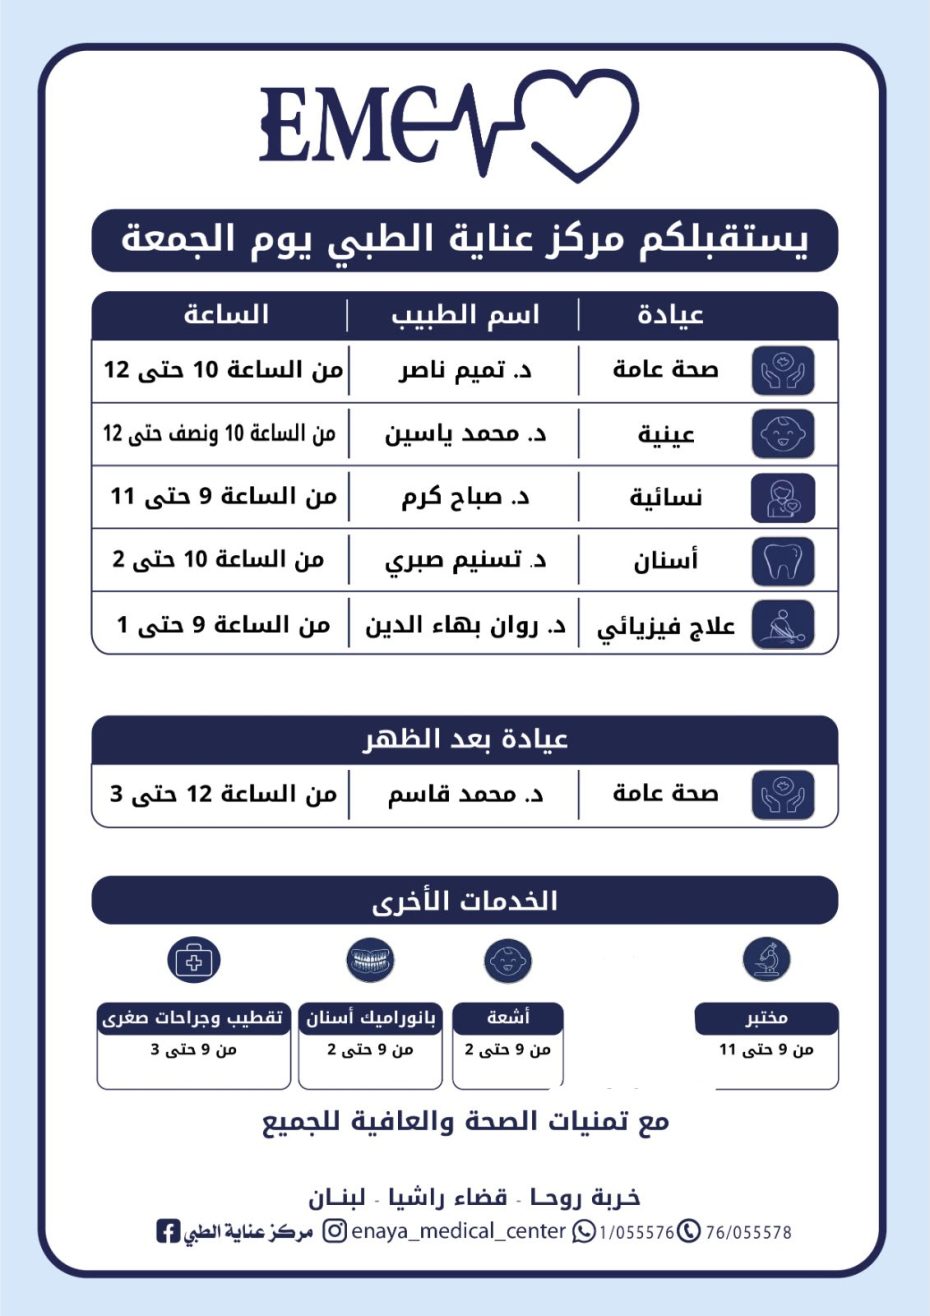

مركز عناية الطبي: دوام الأطباء والخدمات...

مركز عناية الطبي: دوام الأطباء والخدمات – السبت 13 حزيران صيدلية حرمون

مركز عناية الطبي: دوام الأطباء والخدمات...

مركز عناية الطبي: دوام الأطباء والخدمات – الجمعة 12 حزيران صيدلية حرمون